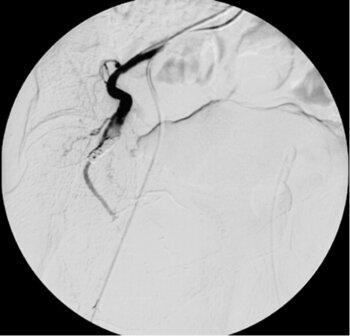

Fallbeispiel Bronchialkarzinom – Spiralembolisation eines blutenden Bronchialkarzinoms (Lungentumor)

CT des Thorax (coronare MPR): Typisch gewundener Verlauf der kräftigen rechten Bronchialarterie, die den Lungentumor versorgt. (MPR=MultiPlanare Reformation)

Angiografiebild: Zu erkennen ist ein Koaxialkatheter in der gewundenen Bronchialarterie.

Digitale Subtraktionsangiografie: Nach Spiralembolisation der Bronchialarterie zeigt sich ein kompletter Verschluss des Gefäßes. Die Blutungen (Bluthusten) des Patienten kamen nach dem Eingriff zum Stillstand.